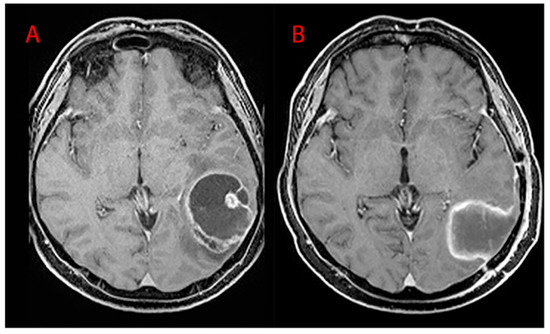

Patients undergoing gross total resection (GTR) had an average OS of 27.61 months (STD 20.38) and a PFS of 11.87 (STD 13.52). The control group underwent a subtotal resection (STR) with an OS of 14.38 months (STD 8.57) and a PFS of 5.30 months (STD 3.77), Figure 3. The Student t-test showed a statistically significant difference between the OS of the two groups (27.61 months vs. 14.38 months, p-value = 0.030), while the difference in PFS was remarkable but not significant (11.87 months vs. 5.31 months, p-value = 0.091).

Figure 3.

OS in patients treated with gross total resection (GTR; in blue) and subtotal resection (STR; in green).

As far as surgery is concerned, the GTR group had significantly higher OS and PFS than the STR group, as widely reported in current literature [15]. Patients with lesions in eloquent areas were treated with STR in order to avoid neurological deficits resulting in a postoperative KPS and quality of life worsening (Figure 8). In our series, none of the patients in the STR group exceeded 36 months of OS, while in the group of patients treated with GTR there were survival rates of up to 85 months (none of the patients were treated with GTR in reintervention after being treated with STR, as reported by Block O et al. [16]). When STR was performed, residual disease volume seemed to be the most important factor influencing OS and PFS [17], being—in our series—an independent prognostic factor. We did not find any difference in terms of survival in patients with residual tumor when the extent of resection exceeded 90%. Our results showed that survival was markedly greater not only in patients treated with GTR as a first intervention, but also in patients who were treated with GTR in reintervention. GTR is hence an independent prognostic factor for survival, even in reintervention cases and even if associated with lower postoperative KPS values in comparison to STR.